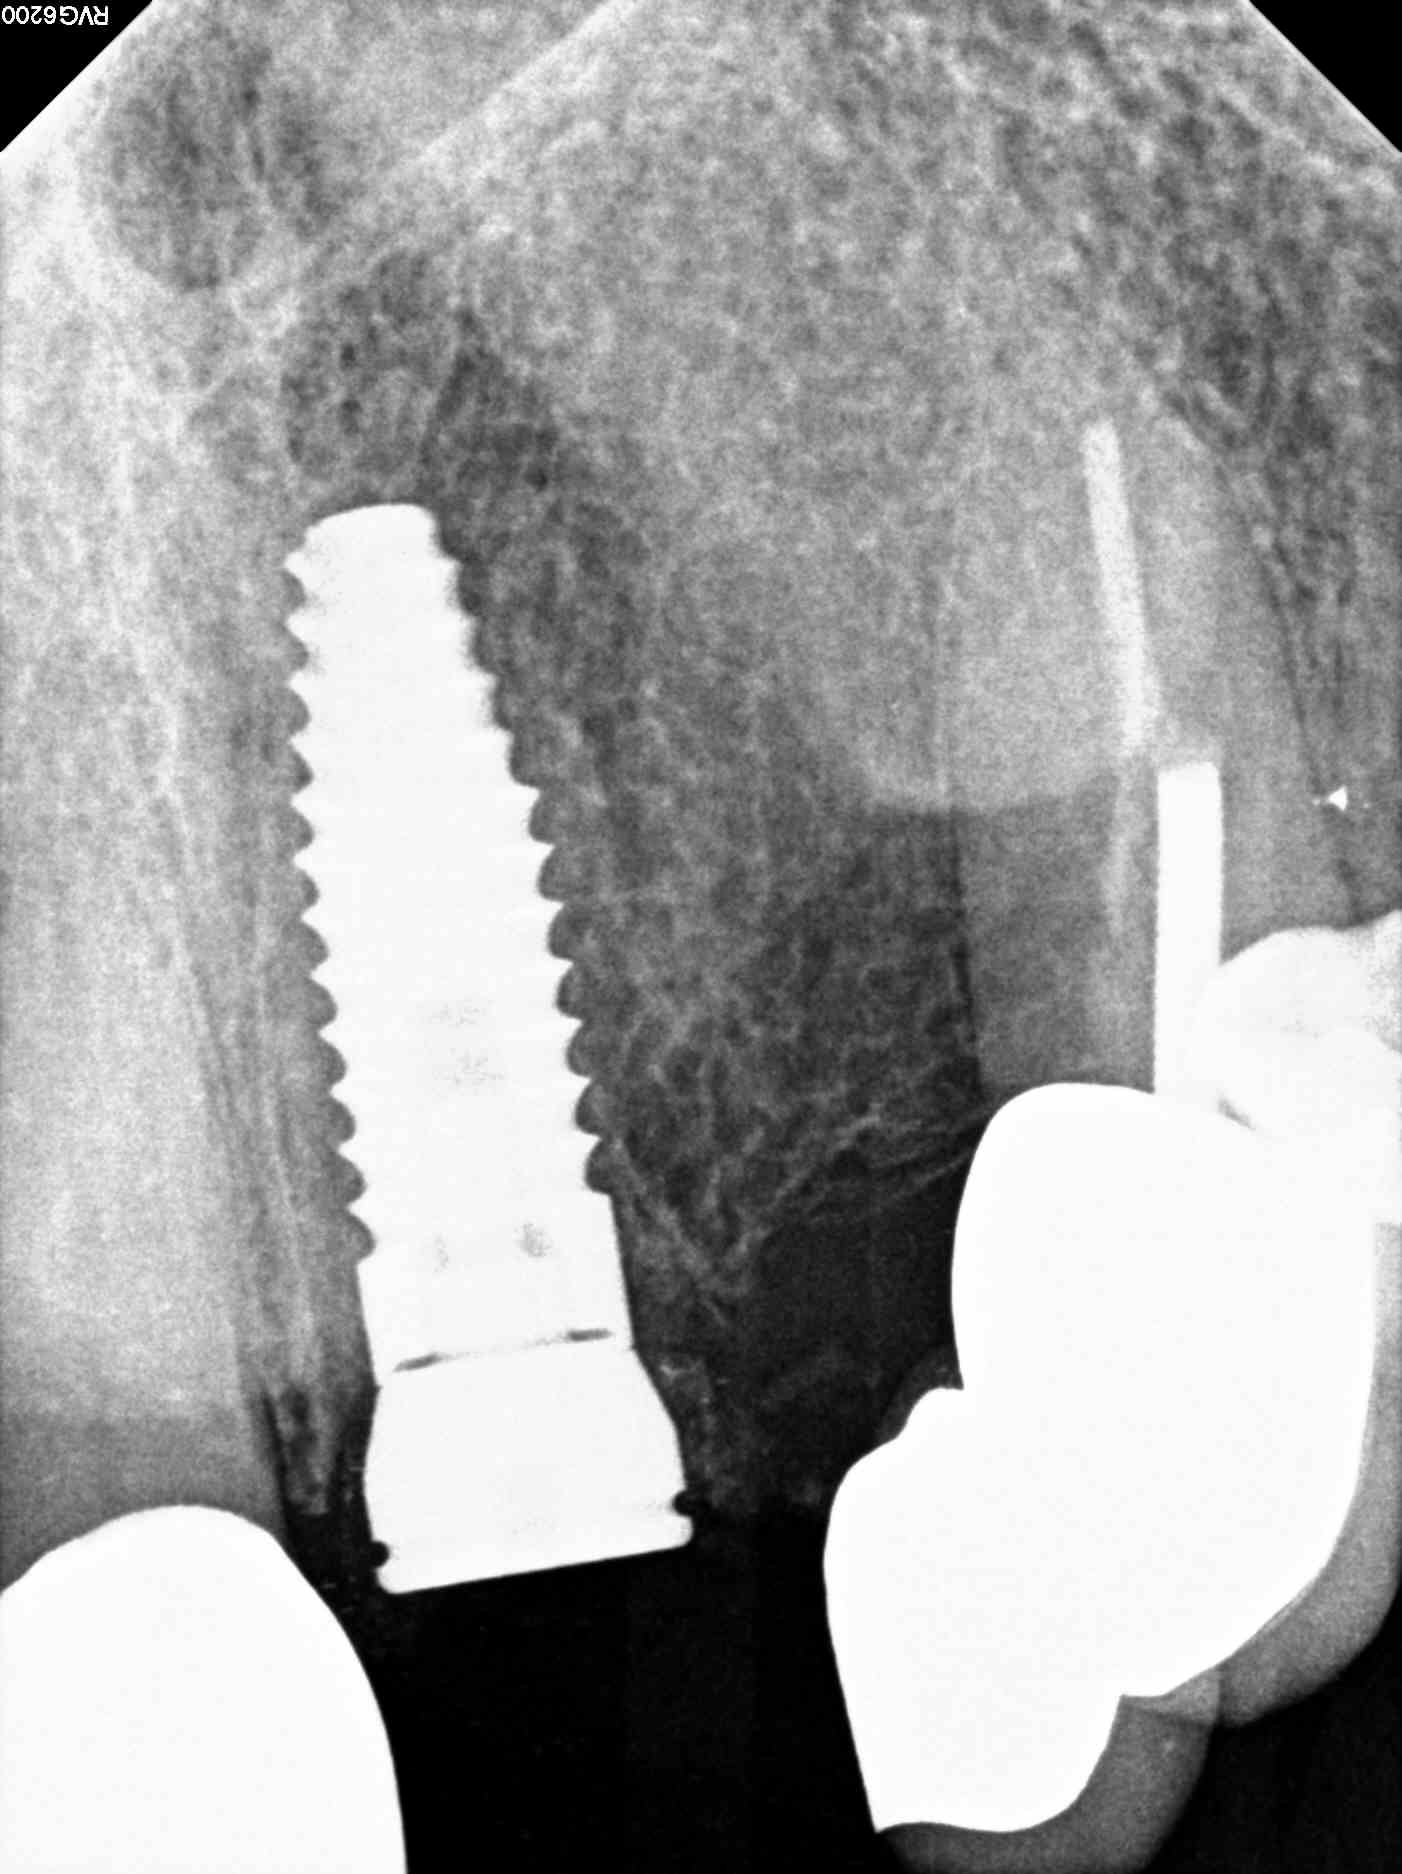

Our geriatric patient had a heavily restored dentition and things were falling apart for her. She needed something both durable and reliable. For teeth #7 and #9, both non-restorable, the best option was immediate dental implant placement and temporary crowns. The teeth were atraumatically extracted and based on the CBCT that was done at our office it was deemed that her bone quantity and quality was sufficient for her to get immediate implants. The case is still in progress and we attached X-rays in this blog of the immediate post-op result. She will be returning in 4 months for final impressions for her dental implants.